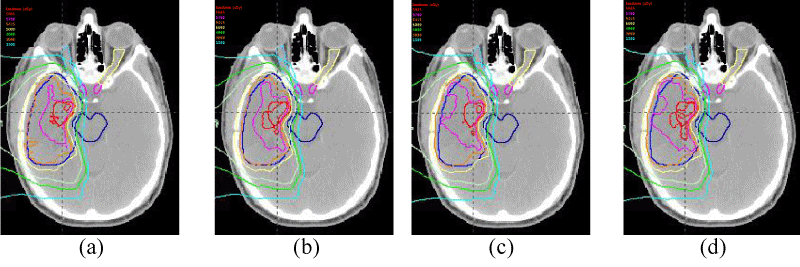

Figure 2 exemplifies iso-dose distributions of the FRBE(a) and the VRBE(b) in the SFO IMPT plan, and the FRBE(c) and the VRBE(d) in the MFO IMPT plan for a patient in figure 1(A). We could not observe visually differences among them. Figures 3 and 4 show dose volume histograms (DVH) of the target volumes such as the GTV and the CTV, and the organs at risk (OAR) such as the brainstem, the optic chiasma, the left optic nerve and the right optic nerve in the SFO IMPT plans for each patient. DVHs in the MFO IMPT plans are shown in figures 5 and 6. Then, Figures 7 and 8 show dose averaged LET LETd volume histograms in the SFO and MFO IMPT for each patient.

Figure 2: Iso-dose distributions of FRBE(a) and VRBE(b) for SFO IMPT plan, and FRBE(c) and VRBE(d) for MFO IMPT plan for patient of Figure 1(A).